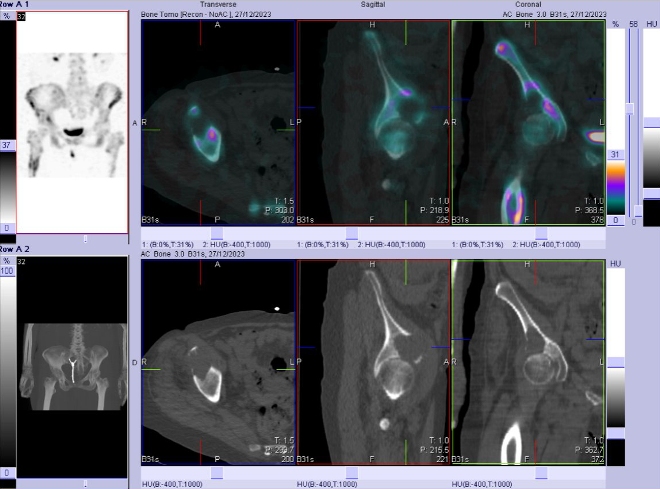

/ Obr. č. 7: Fúze obrazů SPECT a CT pánve. Lytické ložisko v pravé kyčelní kosti.

/ Obr. č. 8-10: Fúze obrazů SPECT a CT bederní páteře, pánve, kyčelních kloubů, proximální části stehenních kostí.

Patologické ložisko vyšší osteoblastické aktivity v proximální části diafýzy pravé stehenní kosti. Osteolytická léze v kosti kyčelní vpravo těsně nad pravým kyčelním kloubem zasahující zčásti i do acetabula, na jejím mediálním okraji je vyšší osteoblastická aktivita.

Nález odpovídá metastatickému postižení skeletu (jak osteolytická, tak osteoblastická metastáza). Degenerativní změny páteře.